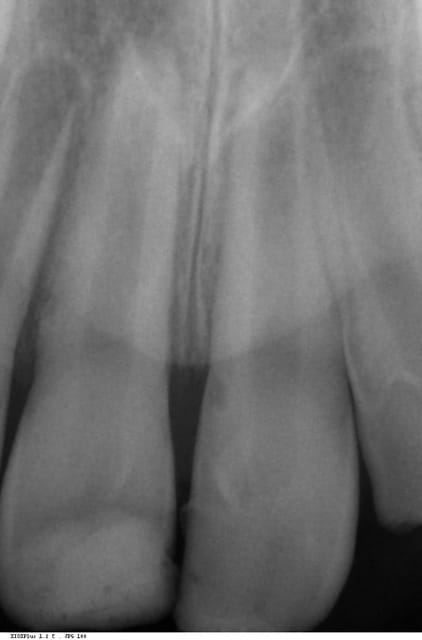

Un enfant de neuf ans a subi un choc frontal en octobre 2013

Fracture coronaire volumineuse de 11, un peu moins 21, et les bords incisaux de 12 et 22. Fracture alvéolaire palatine importante. Dans un premier temps j'ai passé un peu de temps à nettoyer tous les fragments dentaires explosés qui s'étaient glissés sous la muqueuse palatine (un beau lambeau naturel), j'ai protégé avec un verre ionomère la dentine exposée, et j'ai placé un petit bandeau de composite en vestibulaire de 11 et 21 en guise de contention.

Je n'ai laissé la contention qu'une semaine, et j'ai reconstitué les couronnes en composite.

Puis surveillance radio et sensibilité.

à la radio d'abord tout bon, puis un petit truc pas net sur 11 et 21 dans la partie cervicale de la racine. Aujourd'hui abcès en Mésio Vestibulaire de 11, et là, la radio ne laisse pas de doute sur la présence d'une résorption externe radiculaire cervicale. ATB pour l'abcès, mais la suite?

en pièce jointe radio du jour de l'accident, radio intermédiaire, et radio d'aujourd'hui.